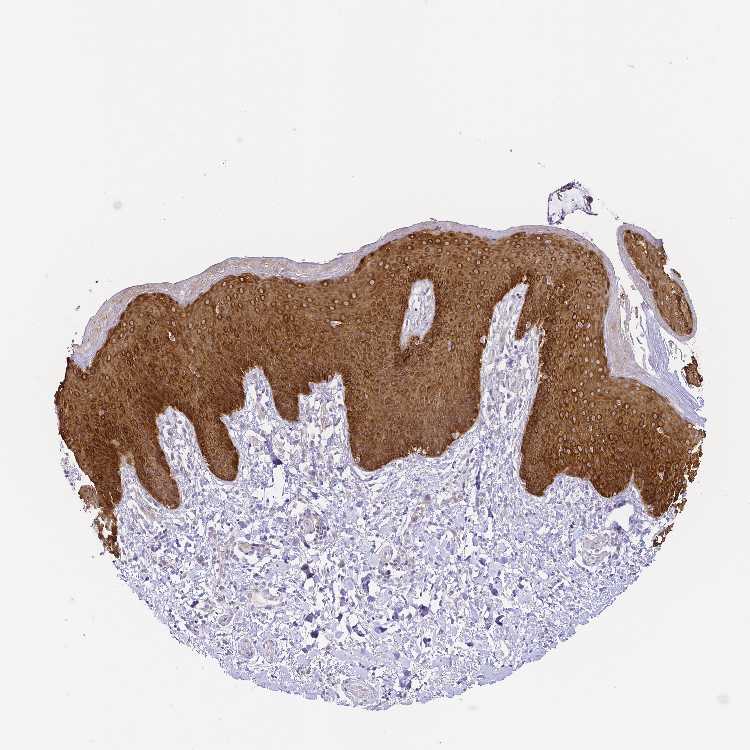

SKIN 1 - Antibody stainingi

Antibody staining in the annotated cell types in the current human tissue is reported as not detected, low, medium, or high, based on conventional immunohistochemistry profiling in selected tissues. This score is based on the combination of the staining intensity and fraction of stained cells.

Each image is clickable and will lead to virtual microscopy that enables deeper exploration of all samples and also displays staining intensity scores, fraction scores and subcellular localization as well as patient and tissue information for each sample.

Antibody HPA062937Antibody CAB012993

Langerhans High-

Cells in basal layer -Medium

Cells in corneal layer -Not detected

Cells in granular layer -Medium

Cells in spinous layer -Medium

Endothelial cells -Not detected

Extracellular matrix -Not detected

Fibroblasts High-

Fibrohistiocytic cells -Not detected

Keratinocytes High-

Langerhans cells -Medium

Lymphocytes -Not detected

Melanocytes HighNot detected

Vascular mural cells -Not detected